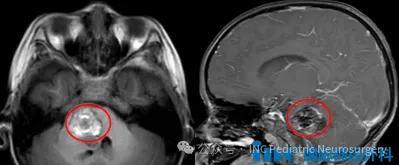

2023年,淼淼的父母发现了孩子的不对劲。嘴角歪斜、流口水、斜眼看人,这些都是儿子从前未曾出现过的表现。在医院的检查下,真相被揭开,原来,淼淼的脑中藏着一个巨大的海绵状血管瘤,如同一个黑洞,吞噬着孩子的健康。 一开始,医生建议淼淼家人立即手术,因为血管瘤已导致脑干出血,再不手...

2023年,淼淼的父母发现了孩子的不对劲。嘴角歪斜、流口水、斜眼看人,这些都是儿子从前未曾出现过的表现。在医院的检查下,真相被揭开,原来,淼淼的脑中藏着一个巨大的海绵状血管瘤,如同一个黑洞,吞噬着孩子的健康。

一开始,医生建议淼淼家人立即手术,因为血管瘤已导致脑干出血,再不手术,极有可能二次出血,到时孩子的各项功能都将受到极大影响,这是手术也无法完全恢复的。

令他们没想到的是,这样看似难得一遇的“好运气”却险些成为儿子的“催命符”。仅1年多后,淼淼第二次脑干出血,情况危急,送到医院时差点被下了病危通知书。检查结果显示:中脑及脑桥出现了新的病灶,巨大的海绵状血管瘤不仅未消,反而合并了大出血!